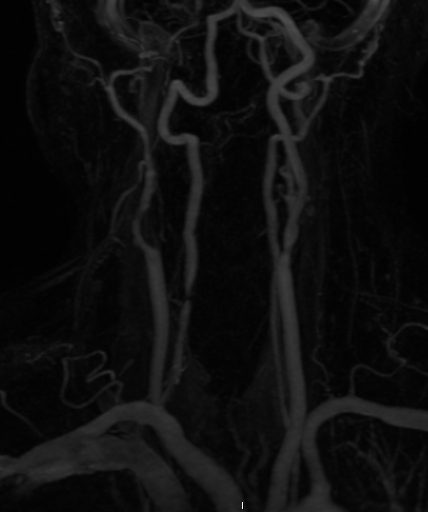

This is the neck MRA of the same patient as above: